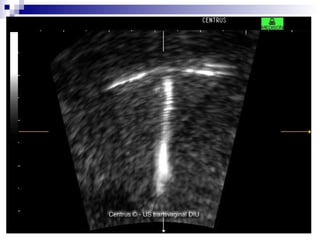

NÃO RECOMENDADOS DIU EM NULIPARAS; NATURAIS EM ADOLESCENTES COM MENOS DE 2 ANOS POS MENARCA; DIAFRAGMA; DEFINITIVOS

DIU